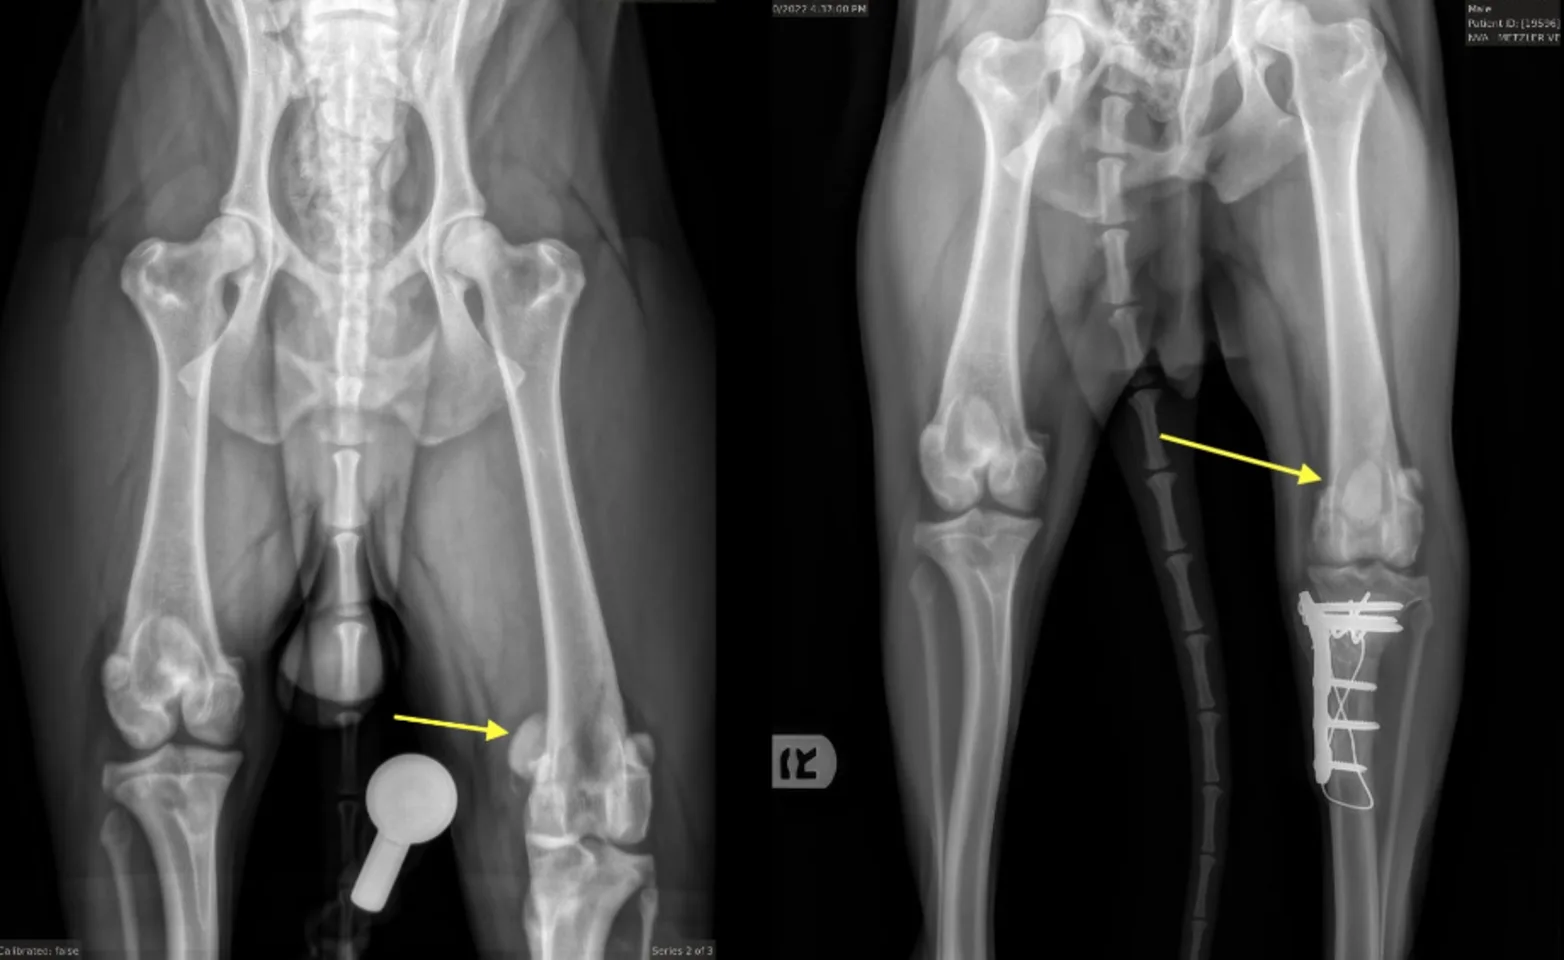

The dog in the image above had a combined CCL tear AND a medially luxating patella. When he came to us he was incredibly painful and would not even use his left leg. Dr. Dorian performed a combined TPLO and MPL procedure to stabilize this dog's knee. You can see the patella in an abnormal location (the yellow arrow) in the x-ray on the left.

In the x-ray on the right (after 10 weeks of healing) you can see the patella is now in a very normal location and this patient is doing incredibly well. You may have also noticed one femur is shorter than the other with a slight anatomic abnormality at one end, but this hasn’t caused our patient any difficulty. We are happy this pup has made an excellent recovery.